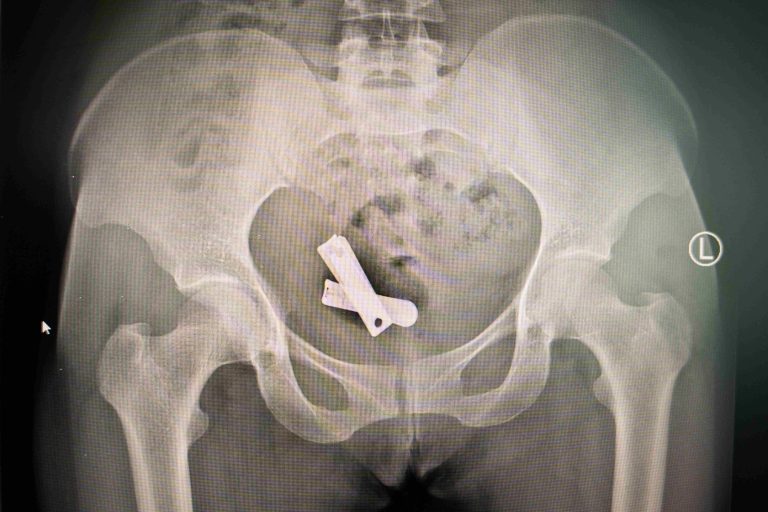

POS MB 708 18X-ray of Eden, war abuse survivor, showing nails inside her body.POS MB 708 18$500